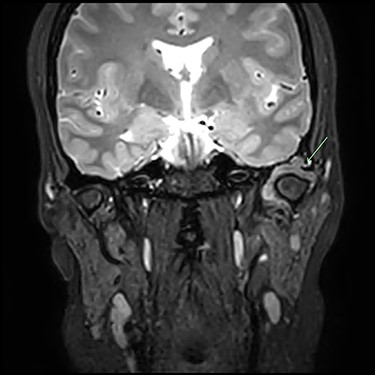

Post-gadolinium T2 MRI TMJs. Coronal view showing marked distension of the superior joint compartment with extensive scalloped lobulated erosion of the left temporal bone (green arrow).